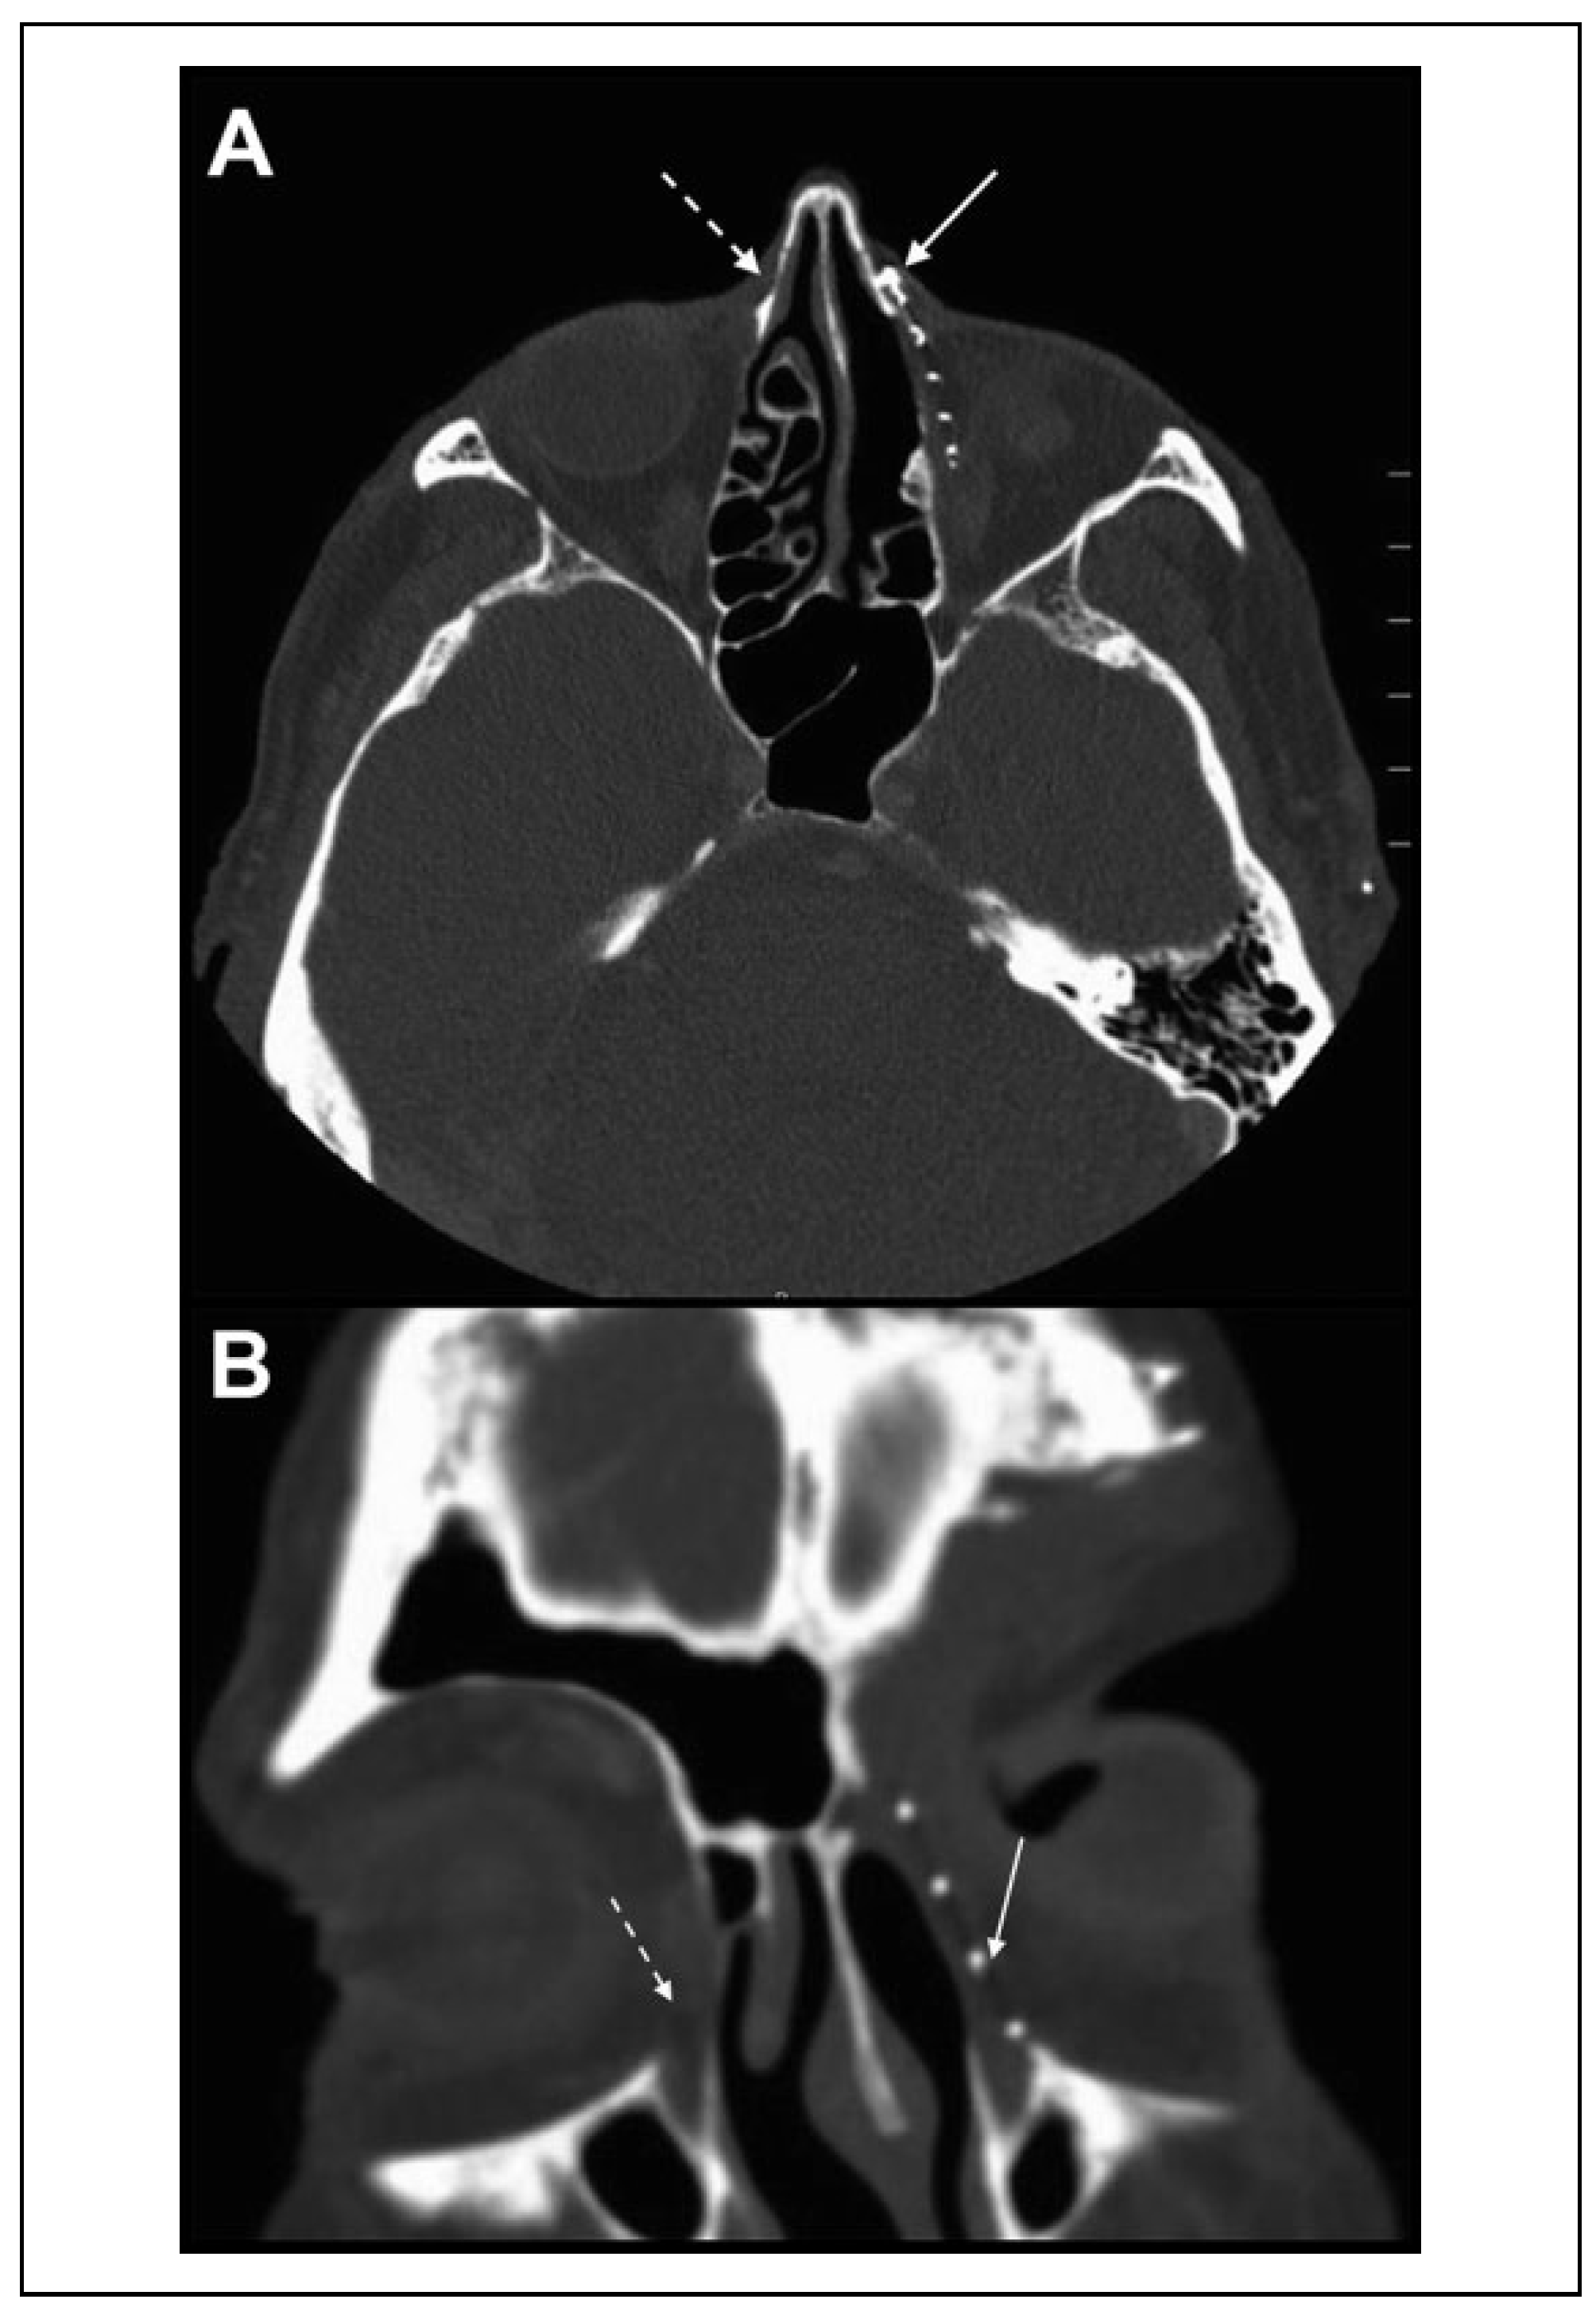

Figure 1. Case 1: CT scan of the orbit on axial (A) and coronal. (B) cuts showing an orbital implant (solid arrow) overlying the post-tumor resection osteotomy. The unobstructed lacrimal sac fossa is seen on the contralateral side (dashed arrow). CT indicates computed tomography.

Case 1: An 80-year-old man was 4 months status-post excision of a left stage T4N0M1 fronto-ethmoidal squamous cell carcinoma (SCC) with extension into the left forehead and left medial orbit. Excision involved removal of the anterior two-thirds of the medial orbital wall up to the frontal process of maxilla, as well as the medial half of the lacrimal sac. Following wide local excision, the medial wall was reconstructed with a titanium-porous polyethylene implant (Medpor Titan, Stryker, Kalamazoo, Michigan) that spanned from the posterior edge of the medial wall defect to the frontal process of maxilla. The implant was fixated anteriorly to the frontal process of maxilla with microplate screws (Figure 1A and B). A bicanalicular Guibor intubation stent was placed through the upper and lower canaliculi and wrapped above the medial wall implant into the patient’s nasal cavity.

The patient presented to the oculoplastic clinic with chronic left-sided epiphora and purulent ocular surface discharge. The patient was diagnosed with chronic dacryocystitis and was scheduled for a left external DCR.

During external DCR, it was noted that the medial wall implant extended along the entire anteroposterior distance of the medial wall of the orbit, overlying the osteotomy created during the prior resection. The anterior third of the implant was rongeured to expose the previous osteotomy and the silicone stents were placed inferonasally through this new passage. The patient was epiphora-free 6 months postoperatively with 100% patent lacrimal system irrigation.